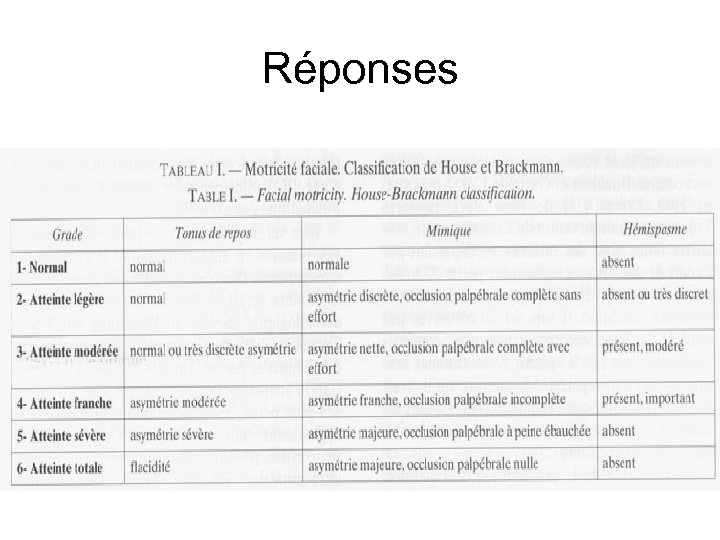

Réponses • Degré d’ablation de la tumeur • Activité electrophysiologique du nerf facial pendant la résection • Réponse à la stimulation à la fin de la procédure chirurgicale • État clinique au réveil • État clinique à la sortie • État clinique à 1 mois, 6 mois, 1 an selon l’échelle de House Brackmann

Réponses • Degré d’ablation de la tumeur • Activité electrophysiologique du nerf facial pendant la résection • Réponse à la stimulation à la fin de la procédure chirurgicale • État clinique au réveil • État clinique à la sortie • État clinique à 1 mois, 6 mois, 1 an selon l’échelle de House Brackmann